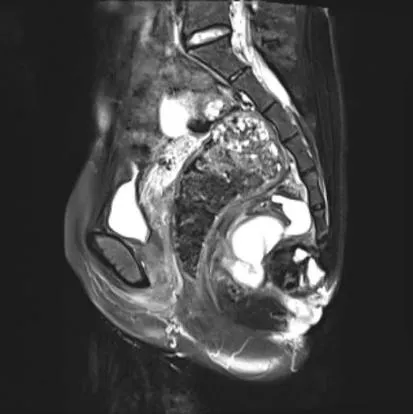

一例因骶尾部肿痛流脓就医的多囊性骶前囊肿患者,在我院肛肠科成功完成手术治疗。

核磁扫描

经专科检查,发现患者肛外有可见陈旧性切口,距离3cm处可见窦道外口,12点可见约7cm愈合疤痕,中段可见破溃外口,骶尾部下方可扪及4cmX2cm条索硬结,3点位可扪及0.5cmX0.5cm包块,轻压痛。